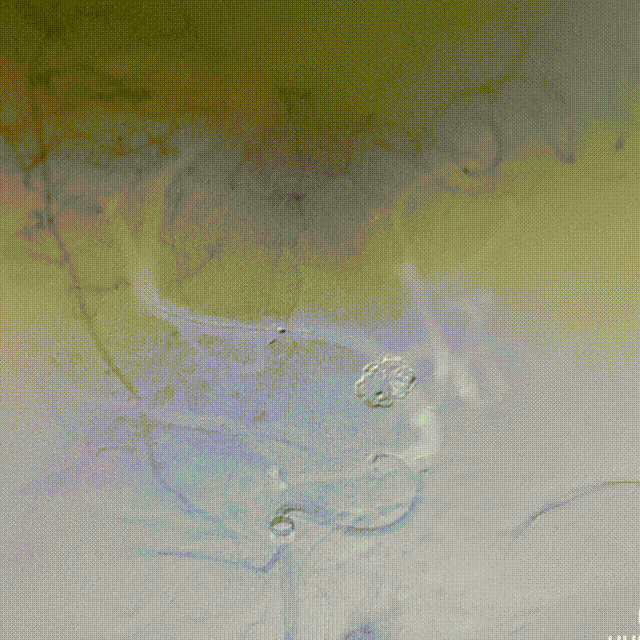

2周复查造影显示:3*3.2mm颈内末端动脉瘤一期采用Atlas支架辅助弹簧圈栓塞术后2周复发,动脉瘤体增大。

复查3D造影显示:3.5mm*4.4mm*3.2mm颈内末端动脉瘤一期采用Atlas支架辅助弹簧圈栓塞术后2周复发,动脉瘤体增大。

3D重建测量:

1)动脉瘤大小6.2*4.7mm

2)FD覆盖长23mm

3)远端血管2.4mm,近端血管3.5mm

动脉瘤的大小在短期内体积迅速增大,证实为血泡样动脉瘤。